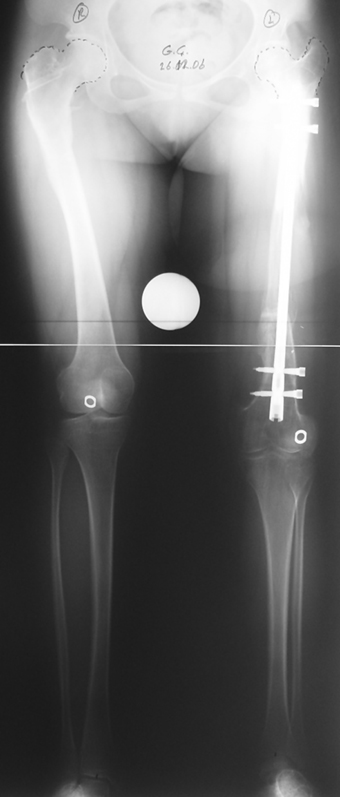

3- POSTTRAVMATİK BACAK KISALIĞI (YANLIŞ KAYNAMA)

Bu Bacak Kısalık tipi bir kırığın kısalmış pozisyonda kaynaması ile oluşur. Bir çok vaka yetişkinlerde görülür ve sadece bir uzatma ile tedavi edilebilir. Ek deformiteler de aynı anda düzeltilebilir. Bu hastaların çoğu çivi üzerinden uzatma veya tam implante edilen çivi ile tedavi edilebilirler.